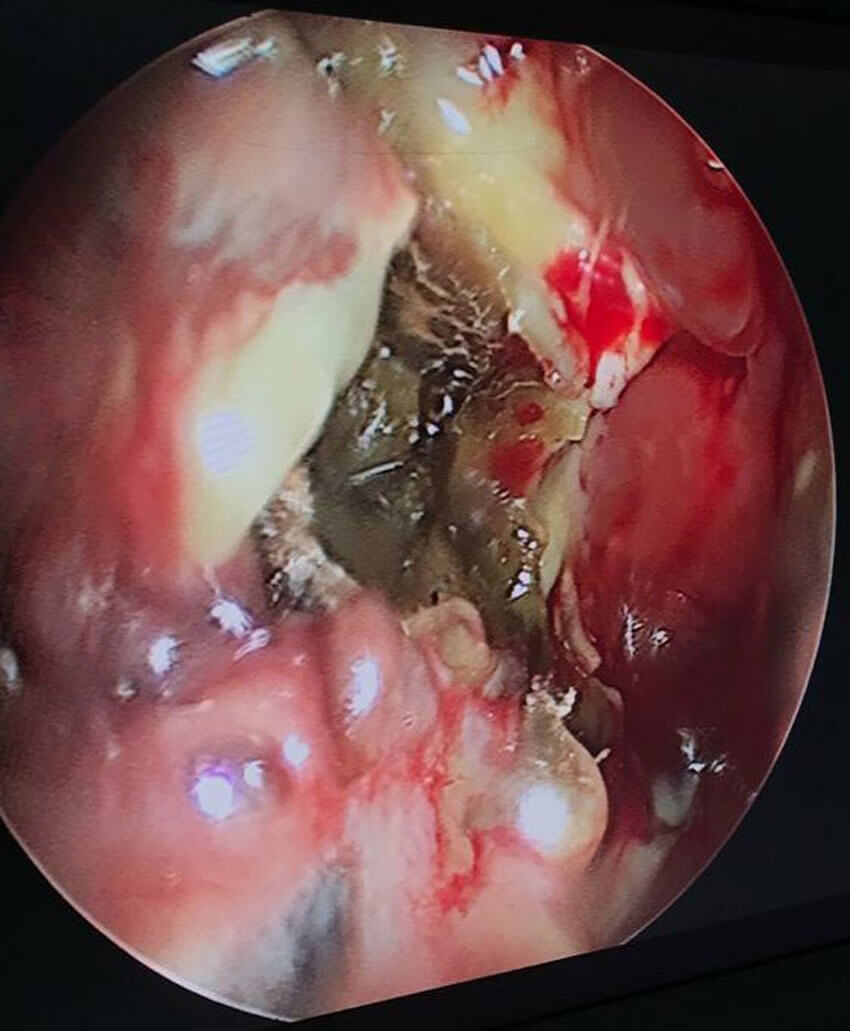

Endoscopic view of pus drained from a frontal lobe abscess through the cribriform plate.